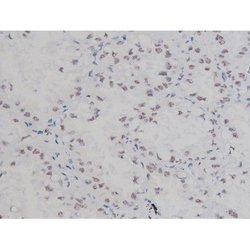

Antibody detects endogenous levels of Nucleophosmin only when phosphorylated at Threonine 199.

| Applications | Immunohistochemistry (Paraffin), Western Blot, Immunocytochemistry |